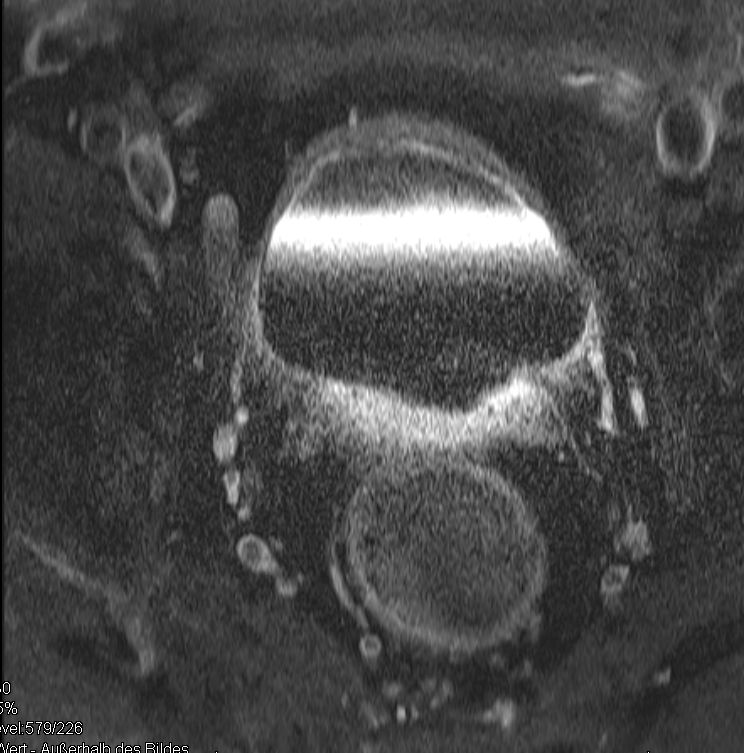

| Tumor | 71-jähriger Mann mit Blutauflagerungen des Stuhls. Sonst keine Symptome.

Das MRT zeigt einen semizirkulär wachsenden, z.T. polypös gestielten Tumor, der das Rektum partiell einengt.![]() |

Darstellung zahlreicher Lymphknoten.![]() | |||||||||||||||||||||||||||||||||||||||||||||||||||||||